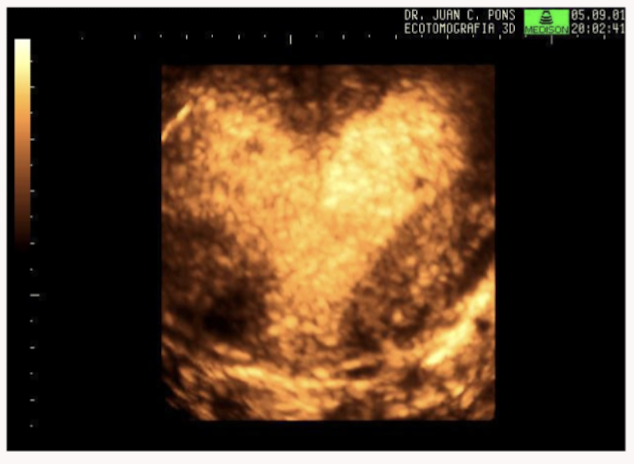

Name the uterine anomaly

Bicornuate uterus: caused by partial failure of fusioon